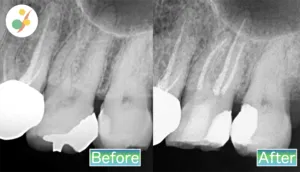

精密根管治療

治療の内容:マイクロスコープを使用した精密根管治療(抜髄)

治療費用:¥88,000(税込み)

リスク:術後に痛みや腫れが出ることがあります。

治療期間:1回